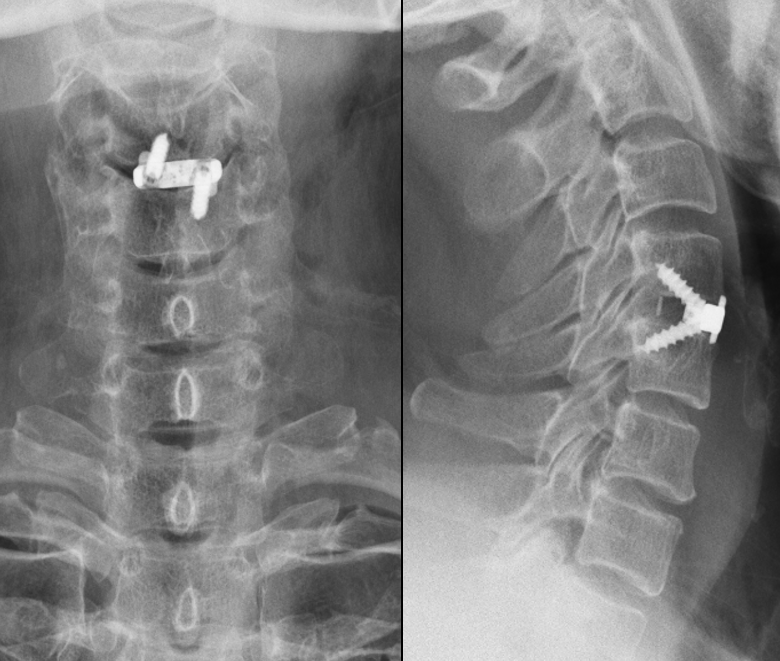

完善术前准备后,在我院行显微镜下颈椎前路手术治疗。我们看一下手术后的影像资料:

可以看到椎管内的压迫已经彻底解除;患者症状明显缓解,上肢肌力及功能恢复正常(本病例为本人治疗过的患者,影像中未显示任何患者的个人信息,请勿转载,如有侵权请联系我)。